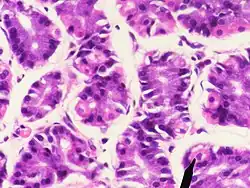

A parietal cell. | |